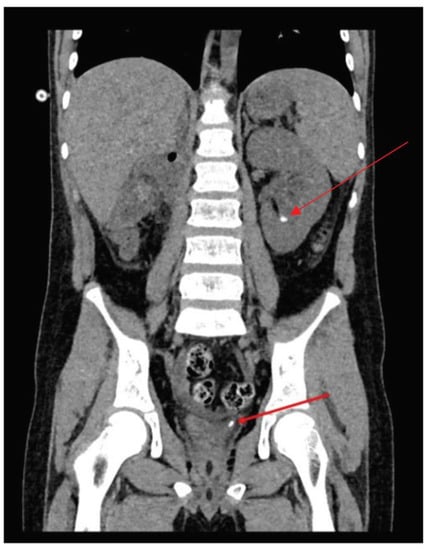

| Diagnosis | Right lung: 5 nodules (5 × 5 mm) Left lung: 2 nodules (4 × 5 mm) Left hilus: 2 lymph nodes (max size 16 mm). | CT and MRI: a tumour in the right kidney (81 × 81 × 104 mm), renal vein infiltration, tumour capsule rupture, right hepatic lobe infiltration, suspected metastases to the right adrenal gland and the peritoneum. ileocecal lymph node (15 × 5 mm) | confirmed active disease process in the same places as in CT/MRI |